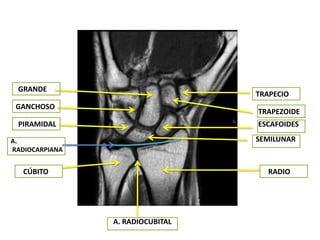

CORTES CORONALES

GRANDE

TRAPECIO

GANCHOSO

TRAPEZOIDE

PIRAMIDAL                        ESCAFOIDES

A.                                SEMILUNAR

RADIOCARPIANA

CÚBITO                            RADIO

A. RADIOCUBITAL